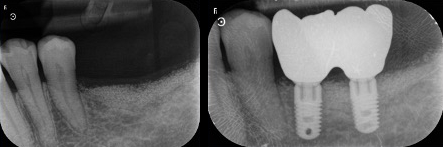

Souvent durant les premières consultations, nos patients référés nous expliquent avoir perdu l’espoir d’avoir des dents fixes à cause de la perte osseuse engendrée par l’extraction dentaire, partant du principe que l’os existant n’est plus suffisant pour accueillir avec fiabilité les implants sans connaître qu’une greffe osseuse et possible.

En effet, une reconstruction osseuse (Greffe osseuse) est indispensable, pour rétablir la hauteur ou la largeur de l’os maxillaire, avant ou en même temps que l’implantation. Ce sont soit les os du patient ou un substitut osseux qui sont utilisés comme matériau de comblement.

Les études nous montrent des résultats extraordinaires avec l’utilisation exclusive ou mélangée que ce soit avec de l’os synthétique ou de l’os autologue (os prélevé dans la bouche du patient pendant l’intervention de reconstruction osseuse).

Il y a plusieurs techniques des reconstructions osseuses et une planification correcte nous donne la possibilité de choisir la technique la plus appropriée pour chaque situation.